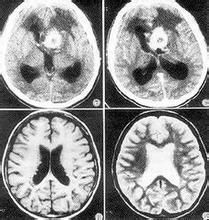

CT表現

①平掃腫瘤呈菜花狀的等密度或混雜密度腫塊。

②腫瘤位於第四腦室時,一般在瘤周可見殘存的腦室;呈帶狀或新月形局陽性腦脊液密度區,幕上腫瘤常發生在腦室周圍,多位於頂、枕葉。

③20%腫瘤有鈣化,呈單發或多發點狀,幕下者多見,幕上少見。

④腫瘤常有囊性變;增強掃描腫瘤呈中等強化。

⑤可發生阻塞性腦積水。

⑥發生室管膜下轉移時,側腦室周邊可見局灶性密度增高塊影或條狀密度增高影。

左起依次是紅細胞、血小板,白細胞其他輔助檢查:頭顱CT與MRI對室管膜瘤有診斷價值。腫瘤在CT平掃上呈邊界清楚的稍高密度影,其中夾雜有低密度。瘤內常有高密度鈣化表現,幕上腫瘤鈣化與囊變較幕下腫瘤多見。部分幕上腫瘤位於腦實質內,周圍腦組織呈輕至中度水腫帶。在MRI上,T1加權為低、等信號影,質子加權與T2加權呈高信號。注射增強劑後腫瘤呈中度至明顯的強化影,部分為不規則強化。間變性室管膜瘤在CT與MRI上強化明顯,腫瘤MRI表現T1W為低信號,T2W與質子加權像上為高信號,腫瘤內信號不均一,可有壞死囊變。室管膜下室管膜瘤在CT上表現為位於腦室內的等或低密度邊界清楚的腫瘤影。在MRI上腫瘤表現T1W為低信號,T2W與質子加權呈高信號影。約半數腫瘤信號不均一,由鈣化或囊變引起。注射增強劑後部分腫瘤可有不均勻強化。